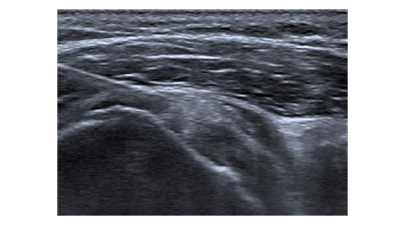

The pillars in the conservative treatment of calcifying tendinopathy are nonsteroidal anti-inflammatory drugs, physiotherapy and prudent use of subacromial corticosteroid injections (SAI). These non-operative therapies are effective in approximately 70% of individuals with calcifying tendinopathy.9 Ultrasound (US) guided needling and extracorporeal shockwave therapy (ESWT) have been proven to be successful minimally invasive treatment modalities when conservative treatment fails (Figure 1 & 2).10,11 Never- theless, failure of these nonsurgical therapies may necessitate surgical treatment in some cases.12

All US-guided needling procedures were performed by an experienced radiologist with a single needle technique without lavage or aspiration. This is common because the goal of fragmenting the calcific depot ensures surface increasement and helps the tendon to remove the calcification itself.14,17,18 The pro- cedure was performed by sterile technique and surgical gloves. First, a diagnostic US examination in the sitting position was performed to evaluate the location and size of the calcific deposits and the integrity of the rotator cuff in the affected shoulder. The skin was then cleaned with a 10% iodine solution and anti- septically draped. After administration of local anesthesia (10cc, 2% lidocaine), the calcific deposit was punctured 10-15 times with a hyperdermic needle under real-time monitoring with US (Figure 3 & 4). There is no evident preference for the used technique,11 single-needling is used in about 50% of recent studies, hence a prevailing technique.19 The final step in the procedure was an injection of a bupiva- caine 0.5% kenacort 10 mg/ml (7:3) mixture into the subacromial space under US guidance.